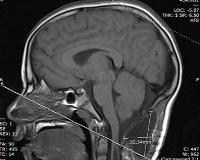

• МРТ головного мозга. С помощью нейровизуализации можно установить наличие, размер, расположение патологической полости в стволе головного мозга. Для оценки движения спинномозговой жидкости, исследования функционального состояния полости используется метод компьютерно-кинематографической МРТ.